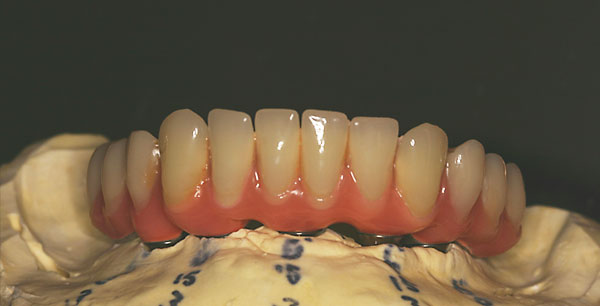

Unterkiefer, fixe Brücke

![]() |